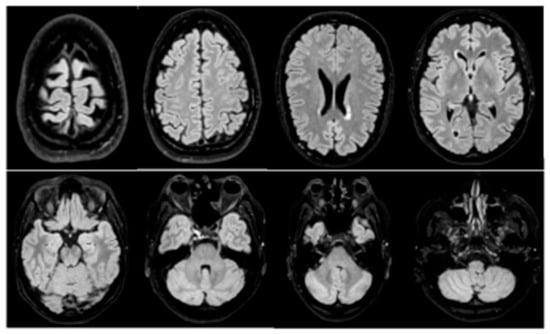

At the time of CSF analysis, a brain MRI was performed, which showed a negative result for brain metastases or meningeal carcinosis [Figure 2].

Figure 2. Gadolinium-based brain MRI: negative for brain metastasis or meningeal carcinomatosis. In particular, no appearance of signal alterations in the cerebral parenchyma both in the supratentorial and subtentorial sites. No areas of diffusion restriction to refer to recent ischemic lesions. After administration of gadolinium, no pathological enhancement of the cerebral parenchyma or meninges. Unchanged morphology and dimensions of the ventricular system. Structures of the median line in axis.